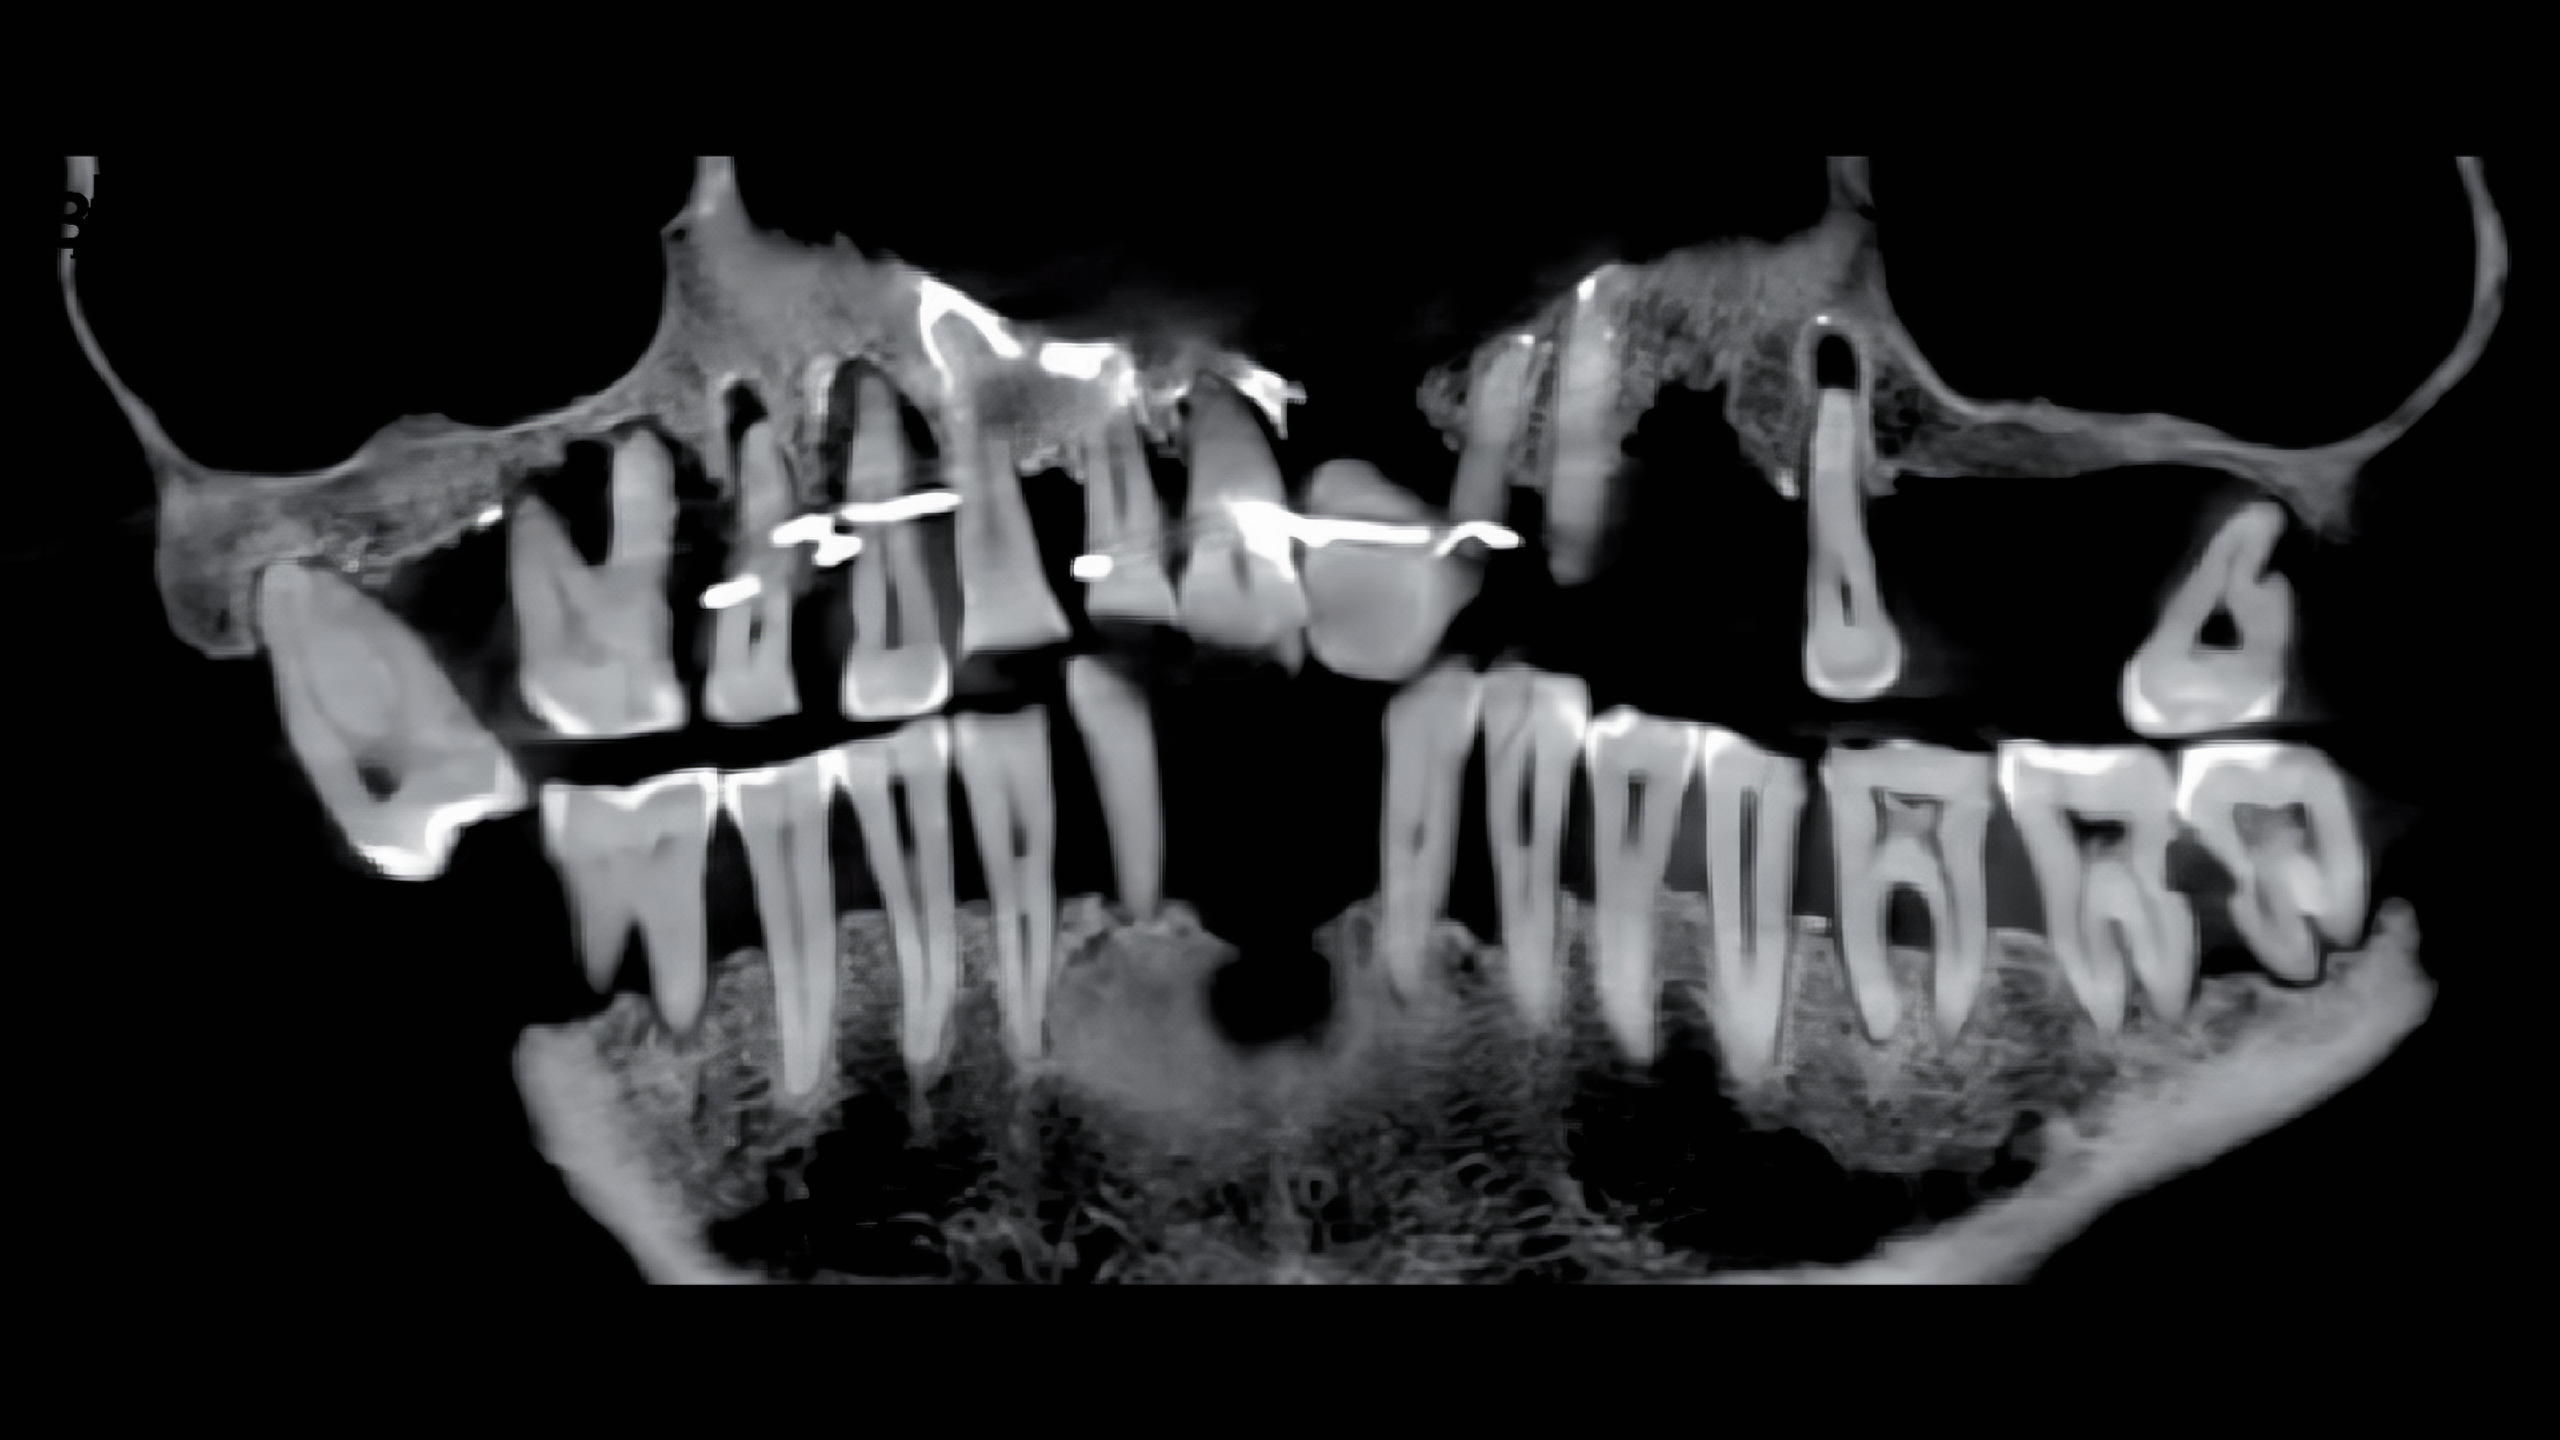

2023년 1월 24일 Journal of Archaeological Science: Reports에 공간된 연구성과에서 X선을 사용하여 3차원 이미지를 만드는 "콘 빔cone beam"으로 그의 두개골을 스캔한 결과 d'Alègre는 심각한 치주 질환periodontal disease을 앓았으며

이때문에 많은 치아가 느슨해졌고 그런 치아가 빠지지 않도록 미세한 금 와이어fine gold wires를 삽입했다는 사실이 밝혀냈다.

이 와이어는 잇몸 근처 치아 바닥을 감았다. 치아 중 일부는 와이어를 넣고자 뚫린 상태였고, 이미 이빨 일부가 빠져 그 부분은 코끼리 상아로 만든 가짜 치아도 넣었다. 임플란트? 시술 비슷하게 한 셈이다.